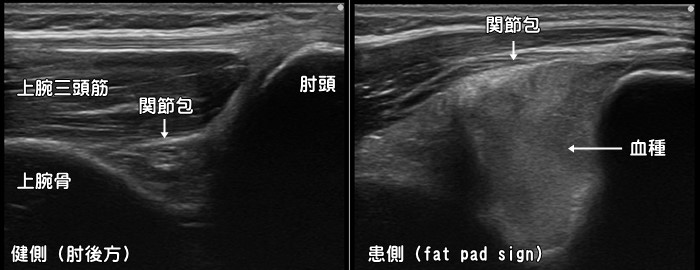

肘関節捻挫・打撲・Fat pad sign

転倒して手をついたり、肘関節を直接強打するなど比較的強い力が加わると関節内に血が溜まります。肘関節は関節包と呼ばれる袋に包まれていてそこに血腫が貯留します。エコーではFat pad sign(ファットパッドサイン)と呼ばれます。Fat pad signが確認された場合、小児では上腕骨顆上骨折、大人では橈骨頭・頚部骨折を強く疑います。レントゲンでは写らない骨折(occult fracture)もあるため非常に重要なサインです。血腫の量が多い場合は針で穿刺・吸引します。